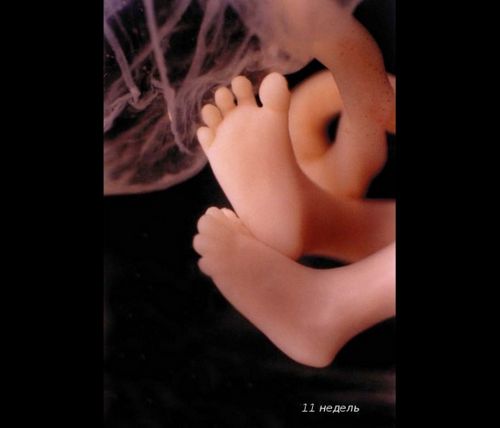

Малюк починає робити перші рухи в маминому животі, однак відчути їх поки неможливо. Тільки акушер через стетоскоп можна почути серцебиття ненародженої крихти. Скоро завершитися "дозрівання" діафрагми, і вона буде брати активну участь в диханні. Замість «хвостика» з'являються сідниці.

На цей тиждень припадає зазвичай перше УЗД вагітної. Статеві органи малюка вже помітні, і лікар в 95% випадком може сказати вам стать дитини.

Його довжина - 10 см. Він важить близько 70 г, як крихітний кошеня при народженні.

Можна добре розглянути личко малюка. Як думаєте, він схожий на тата? Дитина активно моргає, відкриває ротик і удосконалює хапальний рефлекс.